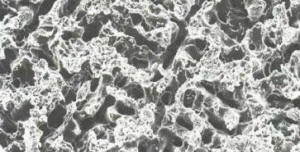

- Grabado electrolítico de una aleación de niquel

cromo, magnificada a 625 aumentos por el

microscopio de barrido electrónico (SEM )

- En este caso se utilizo una solución de ácido

nítrico al 0.5 molar, con una carga eléctrica de 250

miliamperes por centímetro cuadrado, durante 5

minutos. Luego se realizó la limpieza con una

solución de ácido hidroclorhidrico al 18% en una

cuba ultrasónica, durante 10 minutos